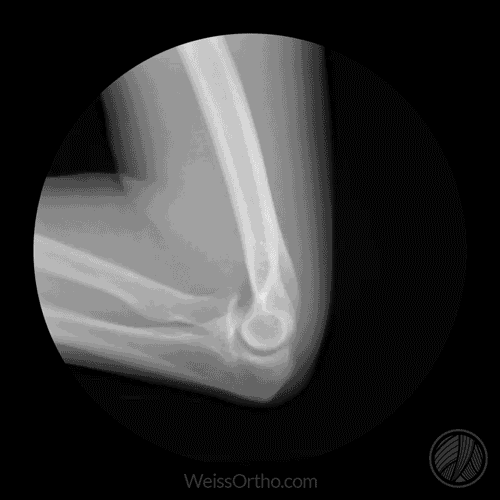

Hinge Joint Movement Gif . They are formed by the. Hinge joints are those that allow movement along one plane. In a hinge joint, protective cartilage. Anatomy, types, and movement explained. It allows bones to move in one plane. It is formed by articulations. The knee joint is a hinge type synovial joint, which mainly allows for flexion and extension (and a small degree of medial and lateral rotation). Explore hinge joints and their unique structures & functions in the body, including ankle, elbow, and knee joints. They facilitate bending and straightening actions, such as flexing a finger. It courses with brachial artery, running from lateral to medial. Lies superficial to brachialis muscle at level of. Medial/lateral cords of the brachial plexus.